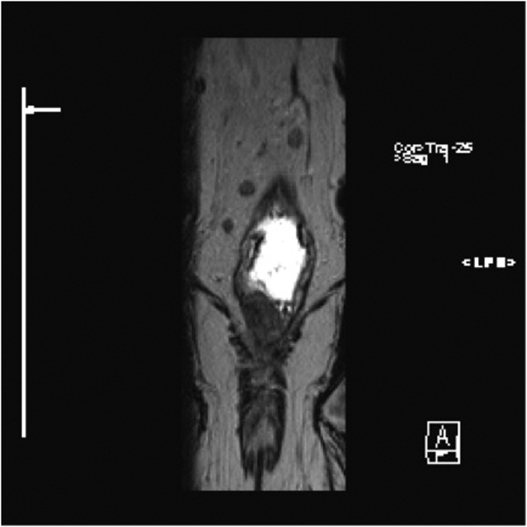

Fig1. Pacient cu neoplasm rectal stadiul IIIC (T3; N2; M0) confirmat bioptic, adenocarcinom mixt G2

a-d imagini T2 ponderate în plan sagital, oblic axial și oblic coronal – masă tisulară dezvoltată superior de joncțiunea anorectală, lateral dreapta, cu minimă extensie la nivelul grăsimii mezorectale și limfoganglioni mezorectali cu diametru de până la 10 mm;

e,f) restricție de difuzie la nivelul tumorii rectale și a doi ganglioni mezorectali

g,h,i) priză de contrast moderată la nivelul tumorii rectale și al ganglionilor mezorectali

j) reconstrucții curbe în planul adevărat al rectului, cu evidențiere mai bună a fasciei mezorectale